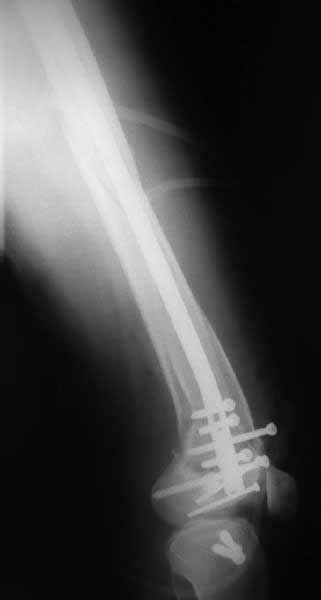

Такое проведение винтов становятся критически важным при переломах типа C3. Где, как правило, без открытой репозиции не обойтись. И пластины тут предлагают больше возможностей - и винтов много, и полиаксиально можно вводить. Иногда гвозди тоже получается использовать. Раз уж колено открыли, то через него и ввести проще, и винты в разных плоскостях с кондуктором удобнее вводить. Так что ретроградные становятся привлекательнее. И большеберцовые, кстати, в качестве ретроградных бедренных очень хорошо использовать.

В приложении пример недавней операции, C3, открытая репозиция, фиксация мыщелков спицами и винтами, ретроградный синтез большеберцовым гвоздем 10,5 мм диаметром, винты 5 мм.

Позволю себе напомнить коллегам ещё раз, что являюсь сторонником антеградного остеосинтеза при переломах дистального эпиметафиза бедренной кости. Такая приверженность основана не на преимуществах внесуставного введения стержня или большем проценте положительных результатов. Она основана на возможности обеспечить блокирование на минимальном расстоянии от суставной поверхности в нескомпрометированной кости и, таким образом стабилизировать максимально низкие переломы. В приведенном Вами случае самый дистальный из блокирующих винтов проведен на расстоянии более 2 см от конца стержня. Из-за того, что к стержню присоединяется кондуктор, на стержне теряется 1-1,5 см его длины, где можно было разместить отверстия для блокирования. И что более важно, вместе с потерянной для этой цели длиной стержня утрачивается для размещения блокировочных винтов, пожалуй, самая ценная часть дистального эпиметафиза бедренной кости. Проблемы дистального блокирования в разных плоскостях, локализации точки ввода стержня при антеградном остеосинтезе – это всё решаемые технические проблемы. Но антеградный остеосинтез низких дистальных переломов бедра при адекватном блокировании в нескомпрометированной кости обеспечивает решение стратегической задачи – стабильный остеосинтез и возможность нагрузки.

В приведенном Вами случае самый дистальный из блокирующих винтов проведен на расстоянии более 2 см от конца стержня.

На этом большеберцовом стержне центр ближайшего к кондуктору отверстия в 14 мм от конца. И пример был про то, что пластина тут, скорее всего, была бы не худшим выбором.